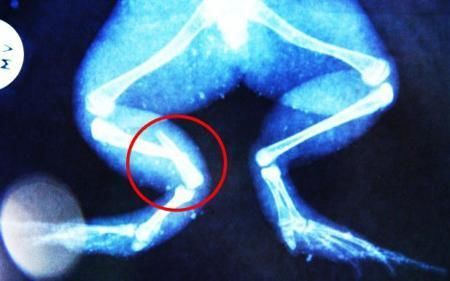

環(huán)球網(wǎng)4月2日?qǐng)?bào)道 據(jù)《每日郵報(bào)》報(bào)道,上個(gè)月,南非大牛蛙布魯萊的右小腿被鄰居家的一只狗咬到,導(dǎo)致粉碎性骨折,現(xiàn)在經(jīng)過(guò)2個(gè)小時(shí)的手術(shù),它的斷腿已經(jīng)被接上,它也因此成為有史以來(lái)第一只通過(guò)外科手術(shù)用鋼針接上斷腿的青蛙。

野生生物專(zhuān)家安妮經(jīng)常為學(xué)校寫(xiě)教材,她認(rèn)為這是人類(lèi)第一次通過(guò)手術(shù)給一只青蛙接斷腿。在手術(shù)開(kāi)始階段,獸醫(yī)把少量給狗用的麻醉藥注入到這只青蛙體內(nèi),讓它失去知覺(jué)。然后他在布魯萊的斷腿上切開(kāi)一個(gè)小口,把一根小鋼針植入腿里。最后獸醫(yī)給它縫了9針,把切口縫合在一起。僅僅幾周后,布魯萊就能在安妮家附近活動(dòng)了。這只青蛙大約已有25歲,主要以嚙齒動(dòng)物、蛇和其他青蛙為食。布魯萊所屬的牛蛙種群正在不斷減小,目前只能在非洲南部的濕地里才能看到這種青蛙。